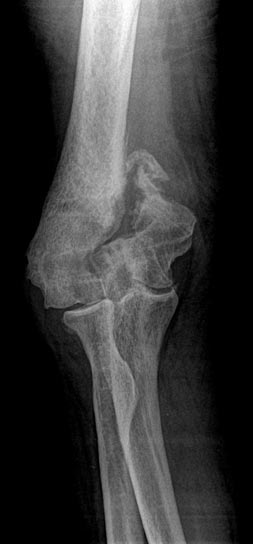

Before Surgery

Displaced Condyle Fracture